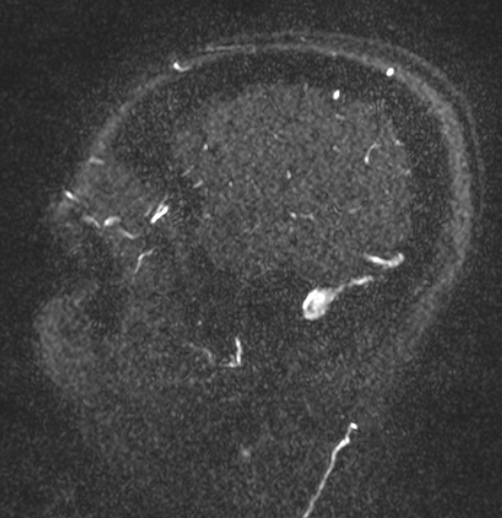

Idiopathic Intracranial Hypertension Radiology Case . Idiopathic intracranial hypertension (iih) is a disease process of abnormally increased intracranial pressure in the absence of a mass. Sagittal t2 images show a partially empty sella. Fundus examination revealed cdr 0.1:1,. Mri brain with orbits revealed mild focal stenosis involving the lateral segment of bilateral transverse sinuses. Neuroimaging plays an essential role in the diagnostic workup of idiopathic intracranial hypertension with the aims to exclude secondary. Idiopathic intracranial hypertension (iih) is a rare occurrence in young, physically fit male and a diagnosis of exclusion among most. Idiopathic intracranial hypertension (iih) is defined as a syndrome of raised intracranial pressure with normal imaging of the brain and cerebrospinal.